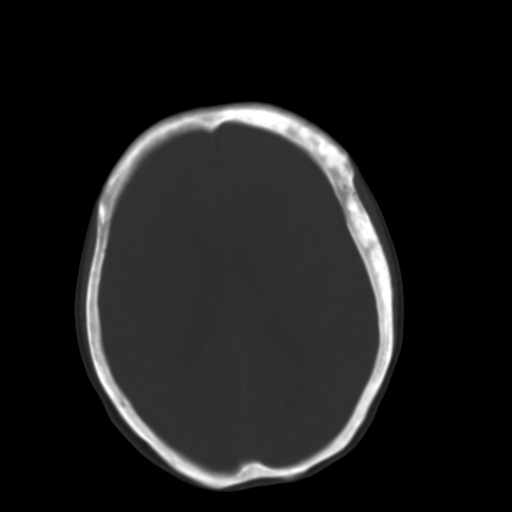

标题: CT17003:F58Y,骨纤维异常增殖征 [打印本页]

标题: CT17003:F58Y,骨纤维异常增殖征

女58y 头晕就诊

左侧额骨增厚,板障层密度增高。 支持骨纤维异常增殖症  。

符合颅骨骨纤维异常增殖症表现。